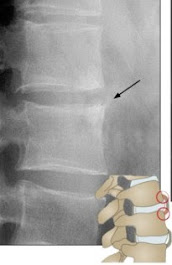

Las figuras 1, 2 y 3 ilustran ejemplos de signo, hallazgo y patrón.

Signo de la C2 ancha. Consiste en un aumento de la distancia entre el margen anterior y el posterior de C2 en relación con C3. Corresponde a una fractura oblicuad el cuerpo vertebral con desplazamiento de un fragmento obre el otro, dando la apariencia de una granda miento del diámetro anteroposterior. Según la oblicuidad de la línea de fractura, ésta puede no verse en la radiografía.